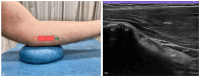

Figure 2.

Patient positioning. (a) Patient seated facing the clinician, left elbow on cushion at 30° flexion for optimal probe access and distal biceps brachii tendon visualisation. (b) Left forearm in a near-neutral position, close to halfway between pronation and supination. (c) Patient lying on side with the left arm slightly off the plinth and the distal humerus supported for comfort and accessibility.